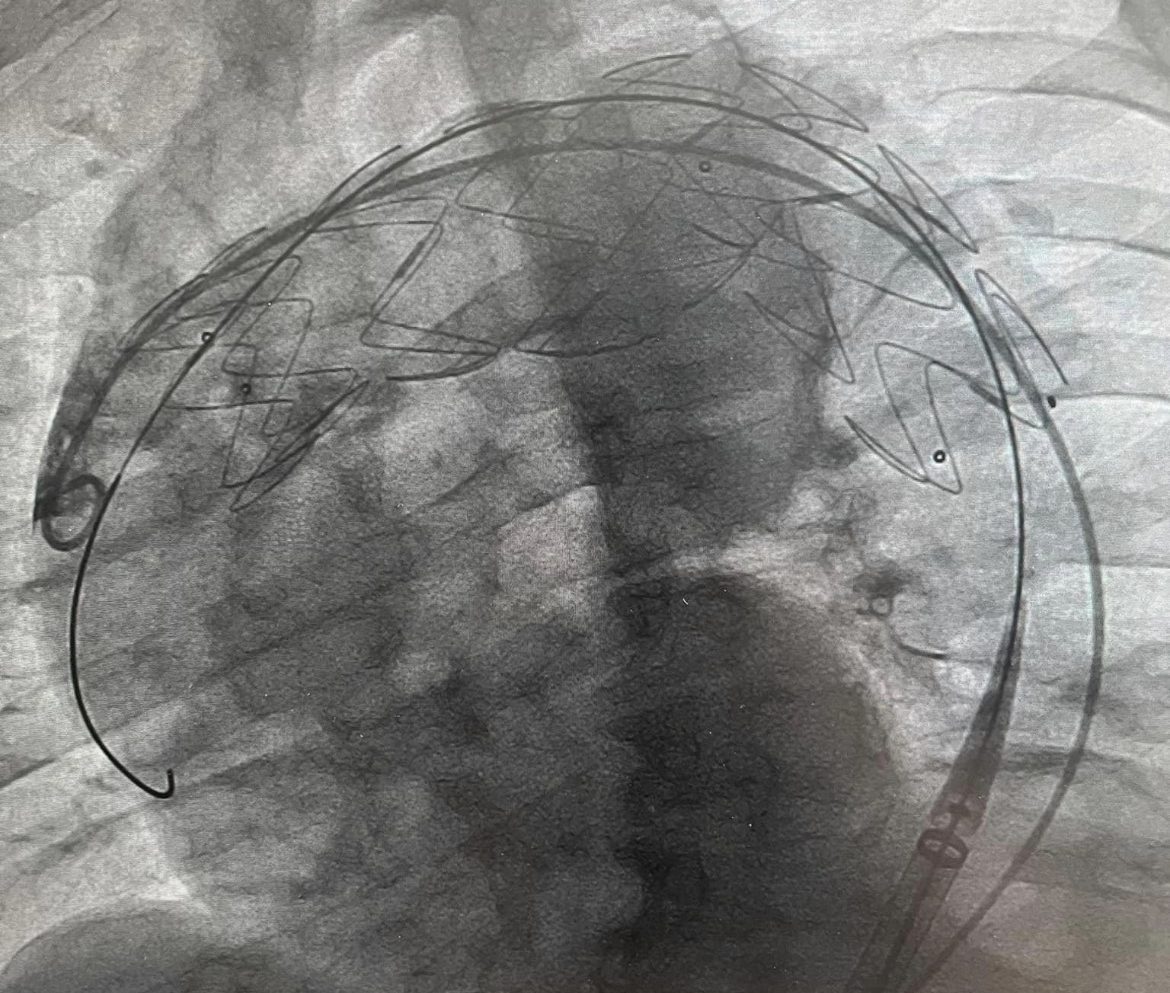

Theo kế hoạch, ê kíp các bác sĩ khoa Phẫu thuật Thần kinh – Lồng ngực và Gây mê hồi sức đã tiến hành phẫu thuật bắc cầu nối động mạch cảnh, chuyển vị từ động mạch cảnh chung phải sang động mạch cảnh chung trái (bên lành) và động mạch dưới đòn trái, để đảm bảo máu được lưu thông và tiếp tục cung cấp cho não, cánh tay… Sau phẫu thuật, bệnh nhân được hồi sức, tỉnh táo và bước tiếp vào phòng can thiệp đặt stent graft để kịp thời xử lý khối phình.

Hình ảnh đặt stent graft cho bệnh nhân D.